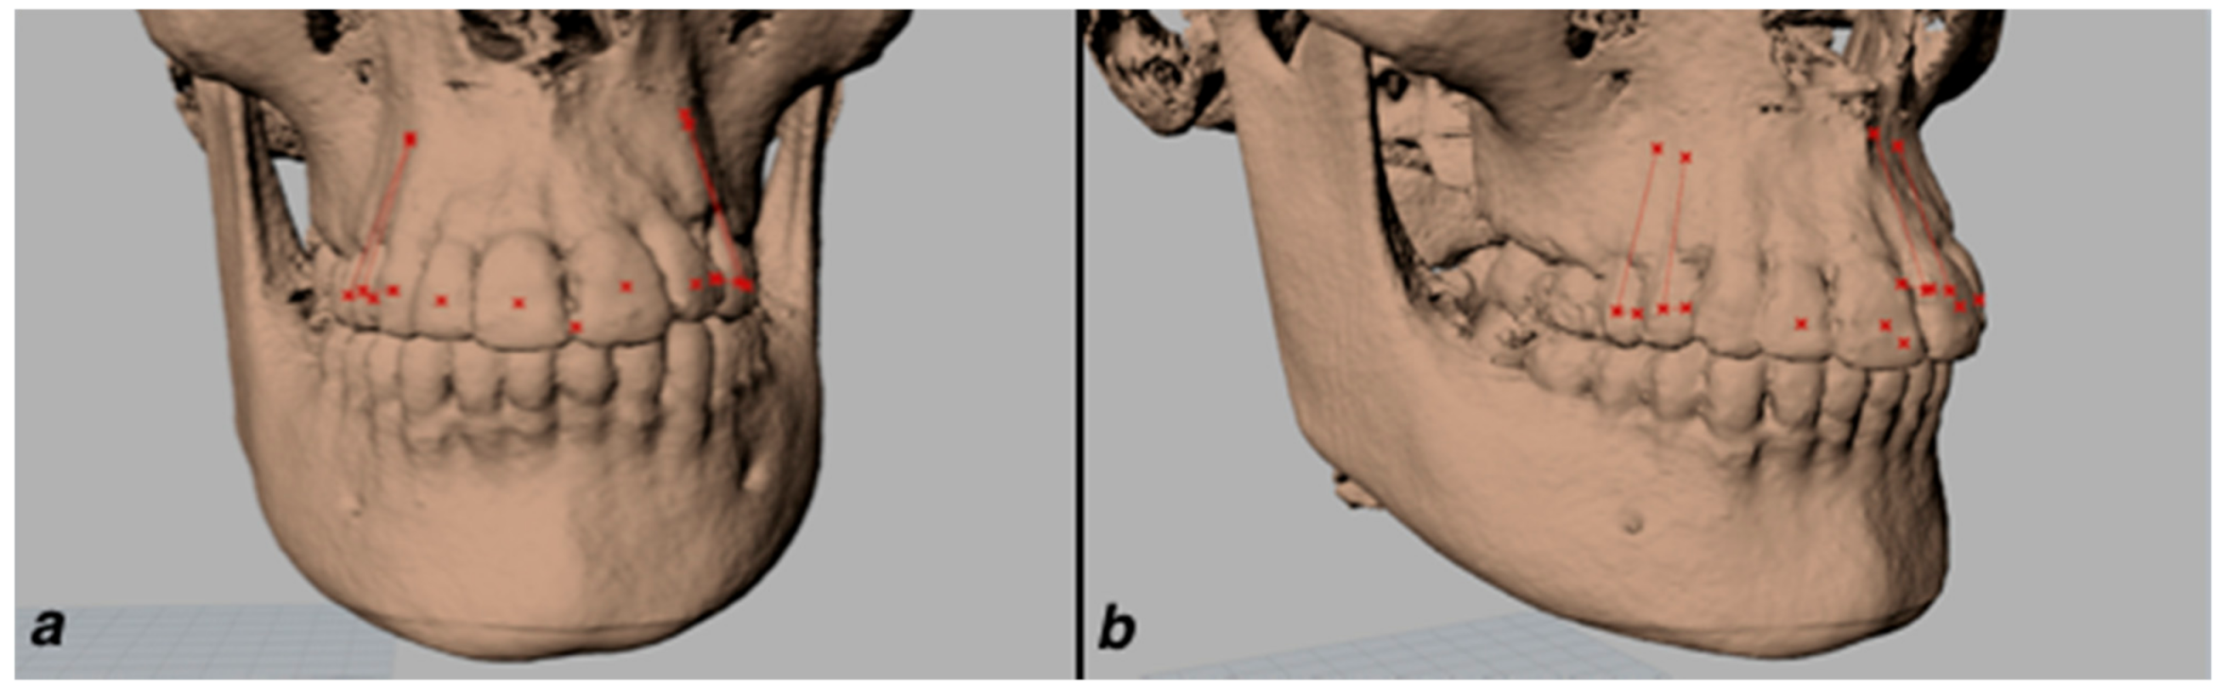

| Landmarks | Definition |

|---|---|

| U6 Fossa | Central fossa of upper first molars right (R) and (L) |

| OB | Point of contact of upper with lower incisors |

| U3 Apex | Apex of upper canine right (R) and (L) |

| U3 Occlusal | Most anterior and lower point of the pulp chamber of the upper canine right (R) and (L) |

| U4 Apex | Apex of upper first premolar right (R) and (L) |

| (when two roots vestibular root apex) | |

| U4 Occlusal | Most anterior and lower point of the pulp chamber of the upper first premolar right (R) and (L) |

| U5 Apex | Apex of upper second premolar right (R) and (L) |

| U5 Occlusal | Most anterior and lower point of the pulp chamber of the upper second premolar right (R) and (L) |

| U1, U2, U3, U4, U5, U6 | Midpoint of Facial Axis Clinical Crown of all the maxillary teeth |